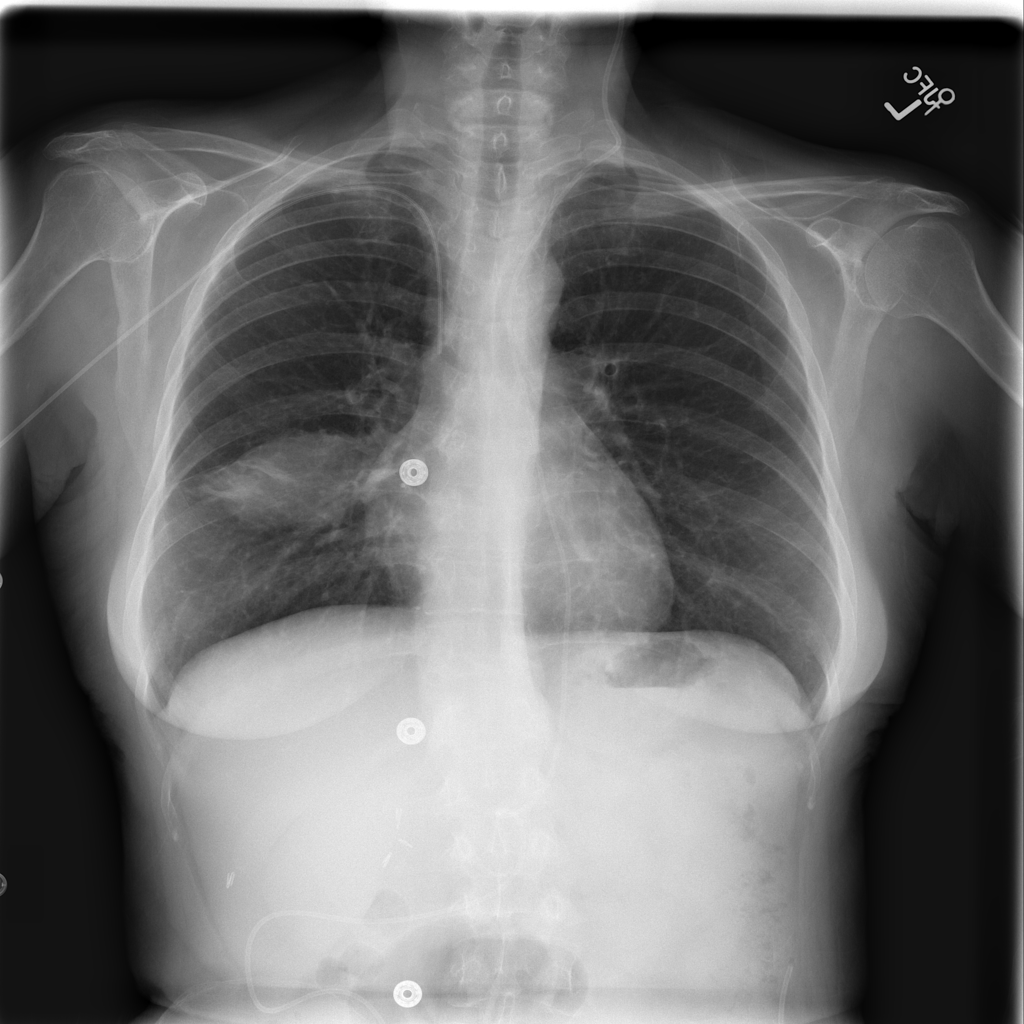

Mass

A mass is a larger focal opacity or lesion seen on the image. It is a descriptive finding that can have several causes and usually needs more imaging or clinical context to characterize.

PAT-4639 · IMG-024Mass

PAT-4639 · IMG-024

AP